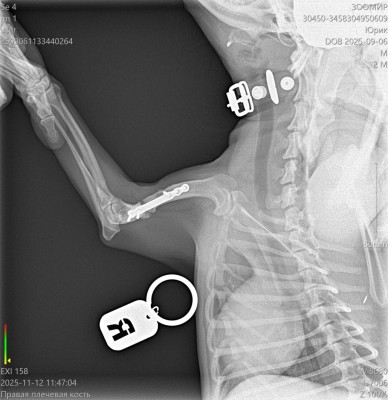

Сделали контрольный рентген - пока мозоли не видно:((((

Теперь через месяц.

Лапой на ровном немного пользуется. Но это за счет пластины.

Рентген